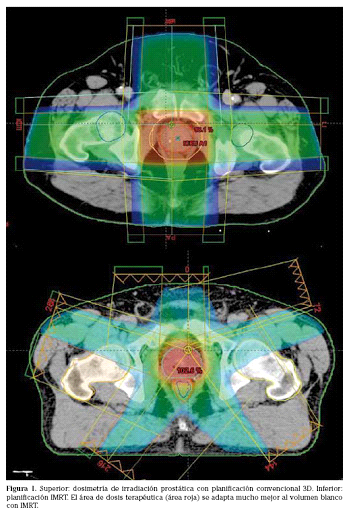

IMÁGENES DE LA EVOLUCION DE LAS DIFERENTES TECNICAS DE RADIOTERAPIA EN LOS ULTIMOS AÑOS

Fig. 1. Técnica de Radioterapia 3D. Se utilizan varios campos de tratamiento y las dosis en OARS son muchos más altas y por lo tanto con mayor riesgo de complicaciones. (Técnica en desuso). Al comparar con las figuras previas, la dosis en rojo sobre la próstata está menos conformada, o sea es un cuadrado en vez de presentar la morfología de la próstata, lo que hace que lleguen mayores dosis sobre los órganos de riesgo como el recto y la vejiga.

Fig. 2. Técnica de IMRT (Radioterapia de intensidad modulada). Se observa como la conformación de la dosis terapéutica protege de manera segura los órganos de riesgo (OARS). La zona de color, muestra la dosis de radiación terapéutica (46Gy) sobre las regiones ganglionares a nivel ilíaco interno, externo y obturatriz. Se evidencia así que las dosis llegan exclusivamente a la zona de interés, respetando la vejiga y el recto.